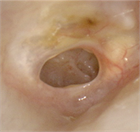

1. 慢性中耳炎の定義:鼓膜穿孔が3か月以上持続し、耳漏を繰り返す中耳の慢性炎症性疾患を指す。世界的には中耳真珠腫を含む概念であることに留意する(推奨度1、RJ)

1. 診断の基本:鼓膜所見による診断が基本であり、必要に応じて側頭骨CTで含気化や陰影を確認する。中耳真珠腫疑い例ではMRIが有用である(推奨度1、RJ)